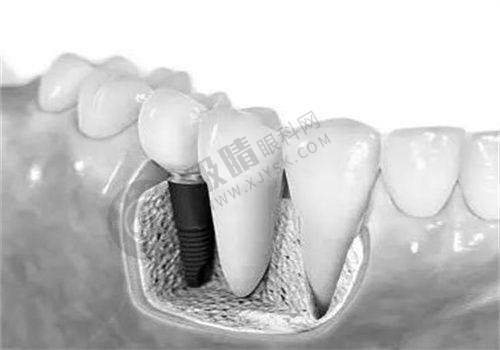

陕西省人民医院口腔科可开展全口数字化种植、ONLY 植骨术、骨劈开术、GBR 手术、即刻种植、上颌窦外提升等高难度的种植技术。

西安交通大学医学校第一附属医院口腔科引入机器人种植(5 分钟/颗)、3D 导板设计,减少人力与耗材浪费;提供3D 数字化模拟矫正方案,提前预览牙齿移动轨迹。

西安交大口腔正畸科提供3D 数字化方案设计,修复科引进德国即刻种植技术

西安瑞泰口腔医院配备数字化等设备,确保诊疗过程的精细与安心,开展种植牙、牙齿矫正等特色项目。